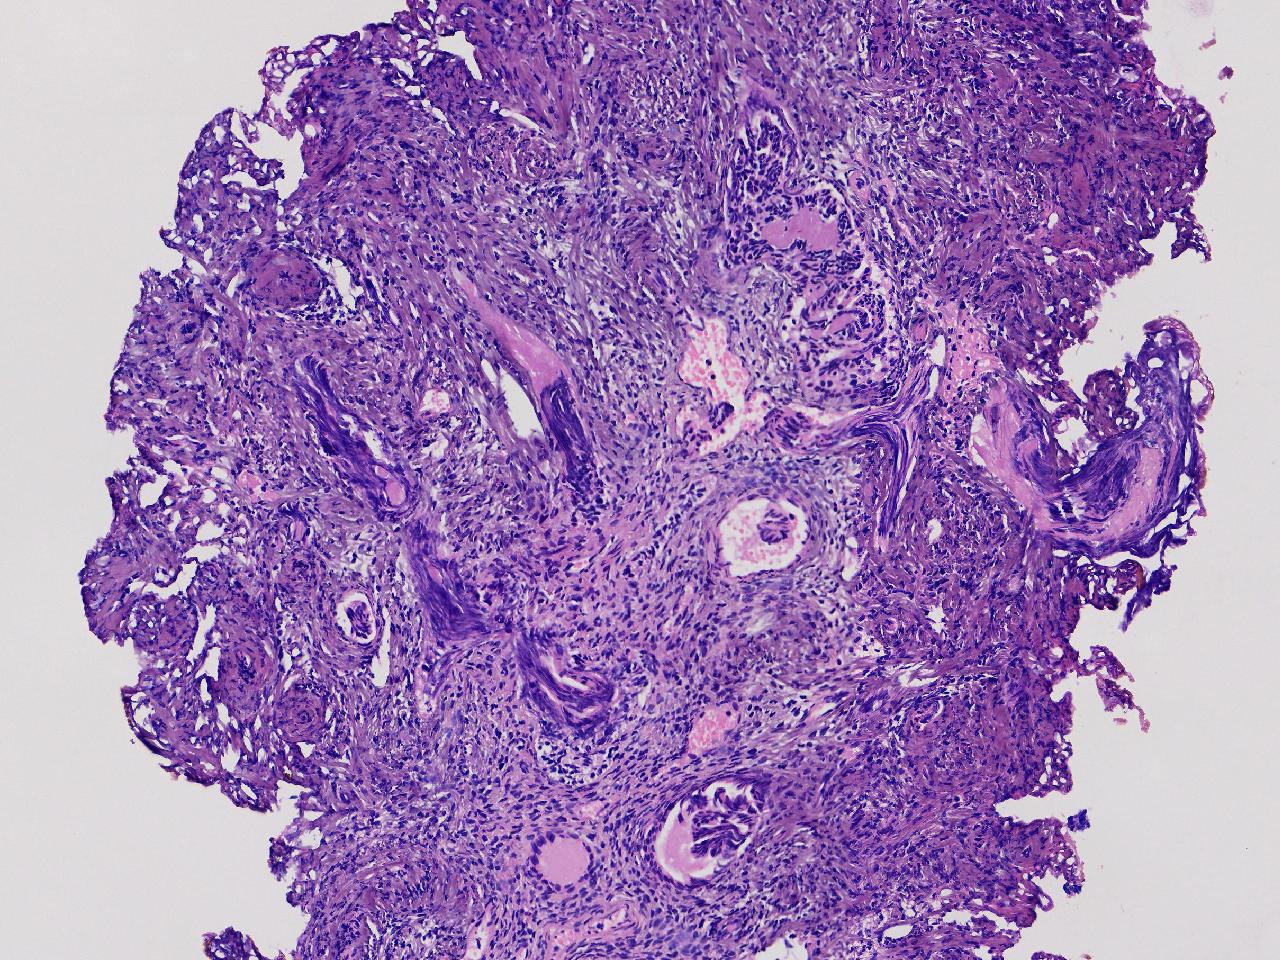

宫腔息肉?

性别

女

年龄

56岁

彩超示宫腔内见5x3ml的团状偏强回声结节,边界清。

灰粉色不整形软组织多块,0.5X0.3X0.3厘米。

首先考虑子宫内膜息肉,有些区域间质细胞较密,找找看有没有核分裂。

彩超提示强声团体积不小,待完整切除送检再综合诊断。